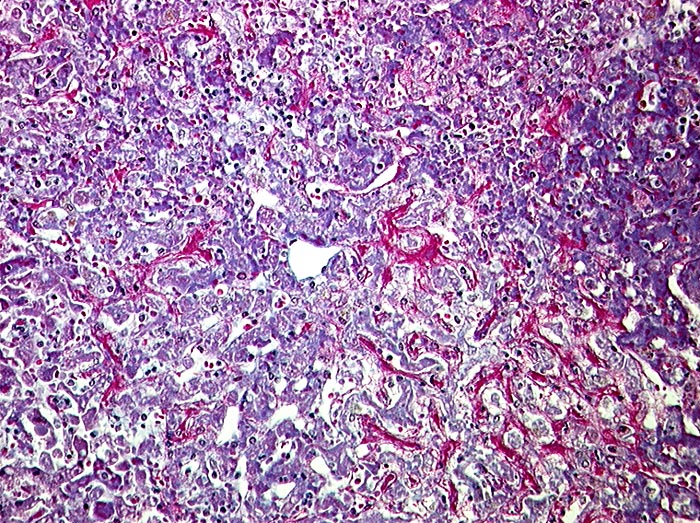

AP/ Subakute Stauung der Leber

Subakute Stauung der Leber

vaskulär / Durchblutungsstörung

Leber, Gallenwege, Pankreas

Leber

Virtuelles Präparat

Pathologischer Befund